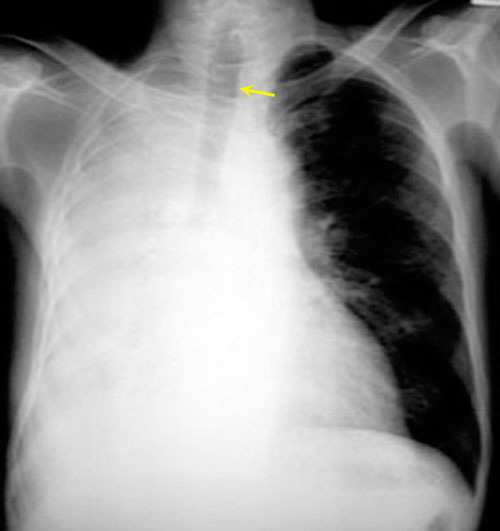

Lobar Collapse Radiology

Jeff alpert reviews the findings of lobar collapse and atelectasis, as seen on chest radiography.

Lobar Collapse Radiology - He reviews how to localize regions of collapse.